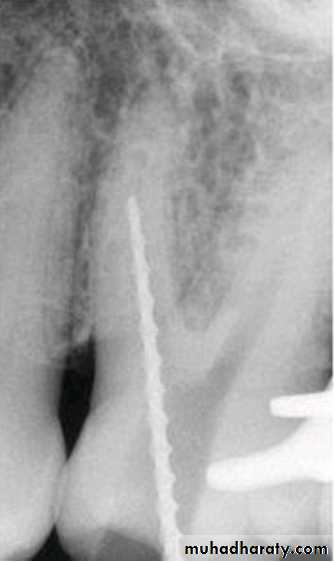

Standardized Technique

Standardized tech. Illustration